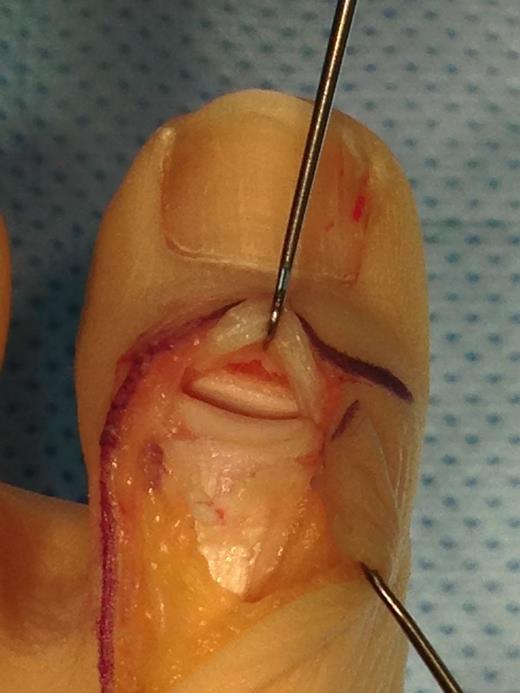

Under general anaesthesia, an L-shaped incision was made to avoid the dorsomedial sensory nerve and avoid injury to the germinal matrix of the nail. The EHL tendon was found to be completely ruptured from the distal phalanx and had retracted back towards the MTPJ. The tendon end was debrided back to healthy tissue and was secured back to the distal phalanx using a Mitek anchor and a non-absorbable suture in a modified Krakow technique. The IPJ was stabilized with a 1.2-mm Kirschner wire (Figs 3–5).

Operative photograph showing ruptured EHL tendon and avulsed IPJ capsule.